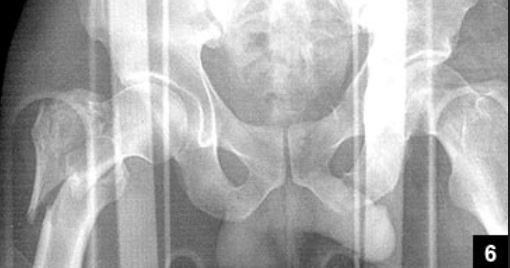

A 24-year-old male sustains the injury seen in Figure A after being thrown from a motorcycle at a high speed. Which of the following fixation methods has been shown to be the most stable fixation construct for this injury?

This is an APC III injury, which is rotationally and vertically unstable with damage to the anterior ring, pelvic floor and posterior ligamentous complex

Sagi showed that optimal treatment is percutaneous iliosacral screw and anterior ring ORIF